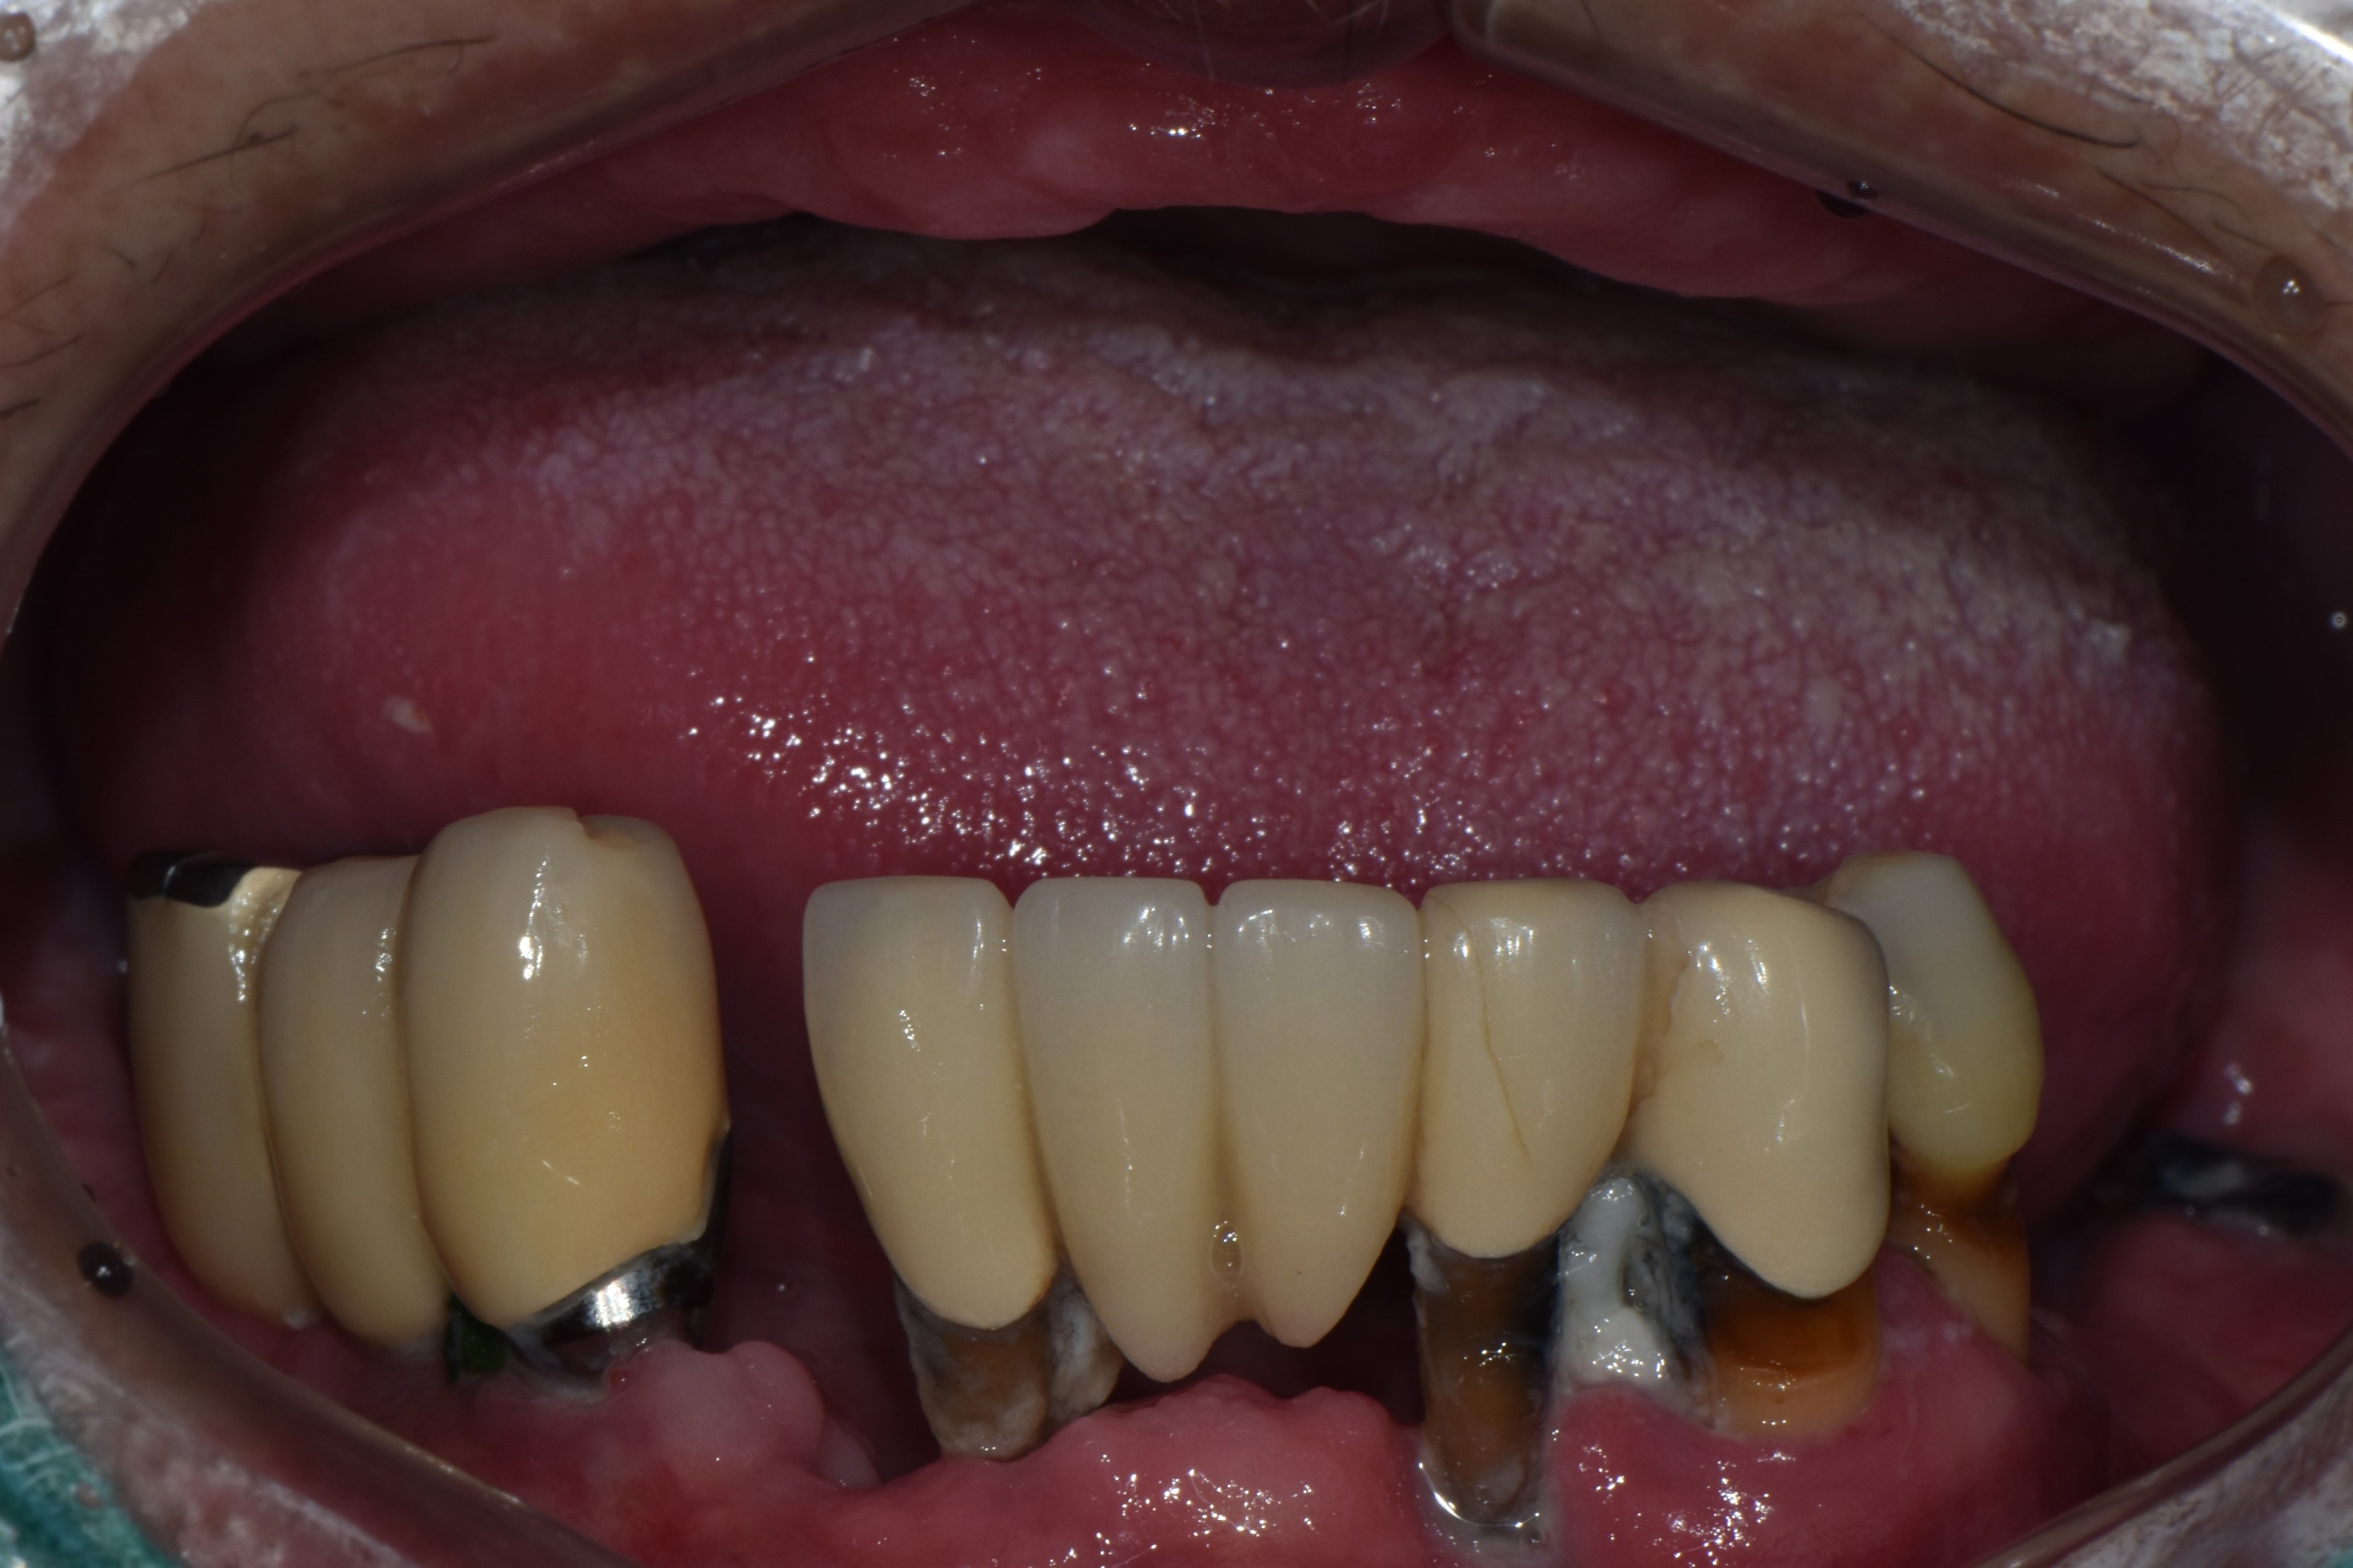

촬영일시: 2024.05.03

[ 치료기간: 2024년 05월 03일 ~2025년 03월 14일 ] ※ 365서울앞선치과의원의 모든 컬럼은 각 진료과 의료진이 직접 작성합니다. 365서울앞선치과의원 임상 케이스 게시물은 환자분께 의학적으로 정확하고 상세한 정보를 드리기 위해 각 진료과 의료진이 직접 작성하며, 모든 증례 사진은 본원 의료진이 직접 시술한 증례를 촬영한 것으로, 의료법 제23조, 제56조에 의거하며 환자분의 동의를 얻어 포스팅에 사용하였습니다. 또한 해당 케이스는 본 환자분의 치료 결과이며, 환자 상태에 따라 치료의 결과는 달라질 수 있습니다. |